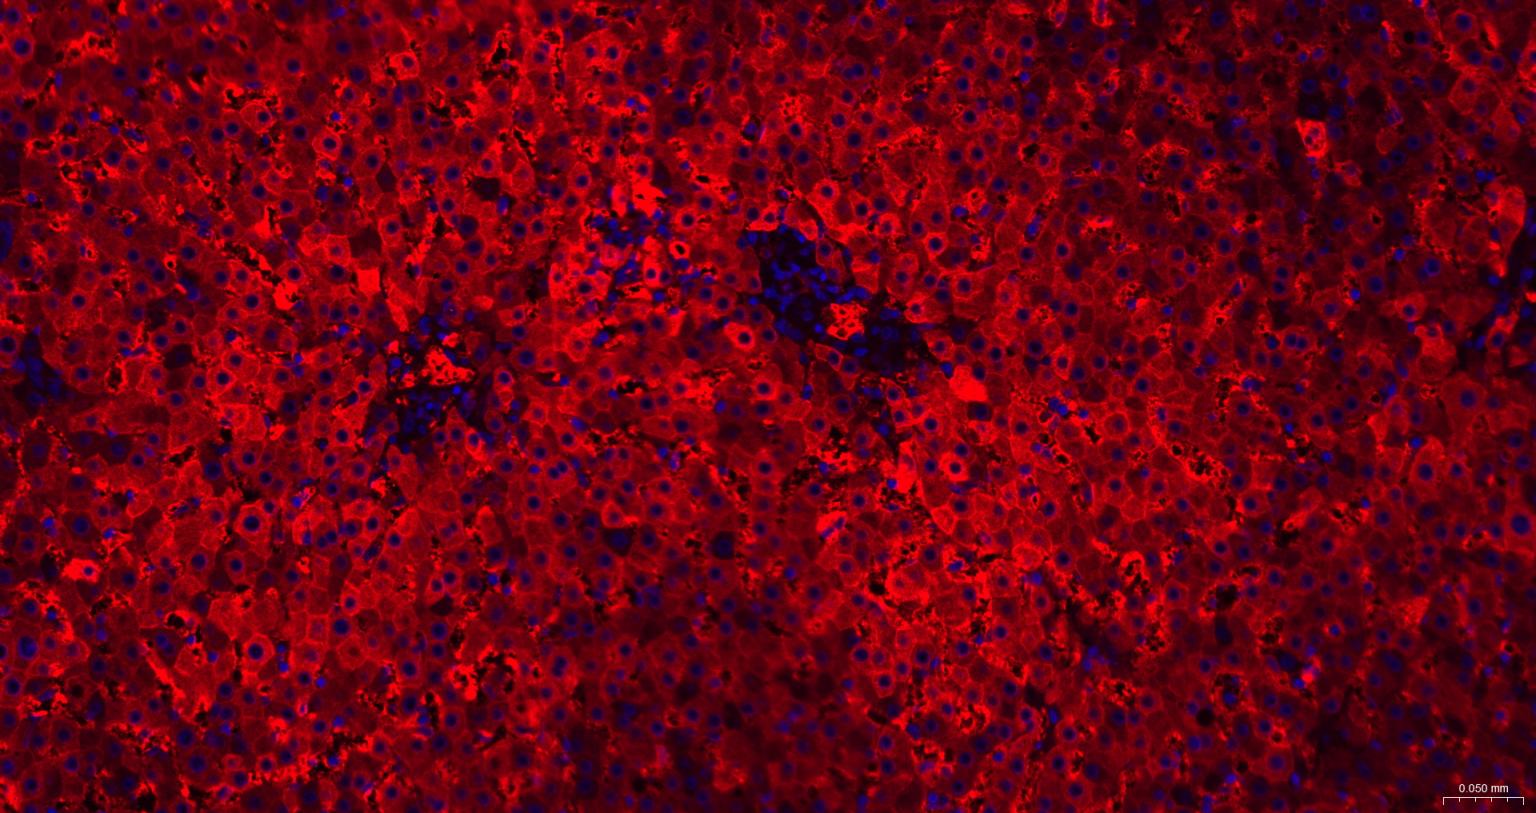

Paraformaldehyde-fixed, paraffin embedded Human Liver; Antigen retrieval by boiling in sodium citrate buffer (pH6.0) for 15 min; The section was incubated with Ferritin Heavy Chain Monoclonal Antibody, Unconjugated (bsm-54108R) at 1:200 overnight at 4°C. Followed by conjugated Goat Anti-Rabbit IgG antibody (Red, bs-0295G-BF594), DAPI (blue, C02-04002) was used to stain the cell nuclei.